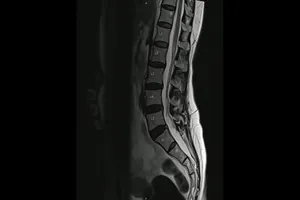

2. 척추 질환

· 허리 디스크, 목 디스크

척추뼈 사이의 디스크가 튀어나와 신경을 압박하는 질환으로, MRI 검사를 통해 디스크의 위치와 정도를 확인하고 치료 계획을 세웁니다.

· 척추 협착증

척추관이 좁아져 신경이 압박되는 질환으로, MRI 검사를 통해 협착된 부위를 확인하고 치료 방법을 결정합니다.

· 척추 측만증

척추가 옆으로 휘어진 질환으로, MRI 검사를 통해 척추의 휘어진 정도와 척수 손상 여부를 확인합니다.